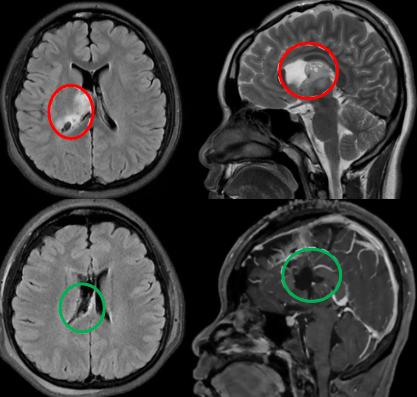

2岁的孩子,一个巨大的鞍区视路胶质瘤,让他的左眼再也看不见颜色。孩子注定要失明了吗?现实并未如此残酷,在父母的坚持下,由巴特朗菲教授主刀,经眶颧入路成功实现全切,病理为毛状黏液样星形细胞瘤。术后1年,他仍在享受着来之不易的童年,而他的小猫也始终陪伴着他度过后续的治疗时光。

7岁时查出脑瘤,第一次手术却只切了绿豆大小的肿瘤,无法确诊、无法二次手术、无法放疗……太多的阻碍让这一家人心力交瘁。尽管她始终无症状,肿瘤却从未停止生长,巴教授表示这正是手术的好时机。所幸,13岁时巴教授为她主刀的手术非常成功,病理为毛细胞星形细胞瘤。1年后,小女孩继续着自己热爱的球类运动,在阳光下挥洒汗水。